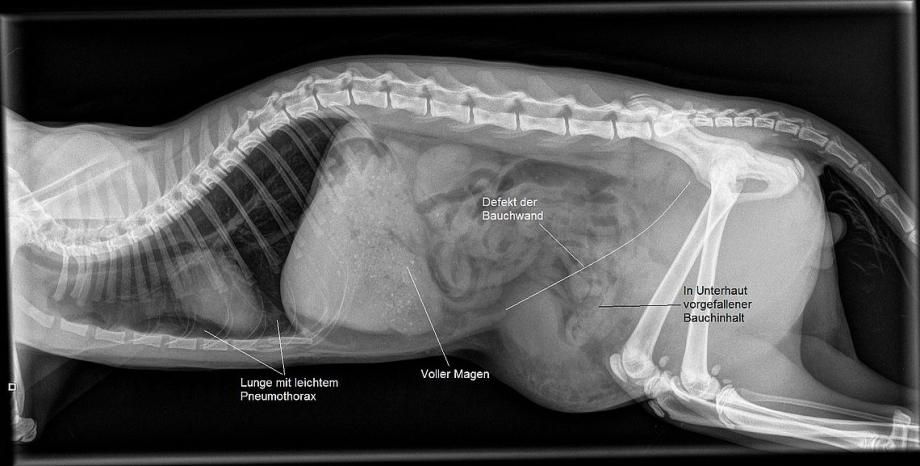

Ein Röntgenbild bestätigt den Verdacht, dass die Katze eine Bauchwandhernie aufweist. Hierbei reisst die Bauchdecke an einer oder mehreren Stellen, und Bauchinhalt wie Därme, Milz und Blase rutschen aus der Bauchhöhle in den Unterhautbereich.

Ausserdem weist Fred einen geringen Pneumothorax auf - aufgrund des Aufpralles hat die Lunge einen Riss erlitten, und Luft ist in den Zwischenraum zwischen Lunge und Brustkorb getreten.

Ein Röntgenbild zeigt, dass sich die Katze offenbar auch eine Riss in der Wachstumsfuge des linken Oberschenkelhales zugezogen hatte, welche sich nun nach einigen Tagen zu einer echten Fraktur entwickelt hat.